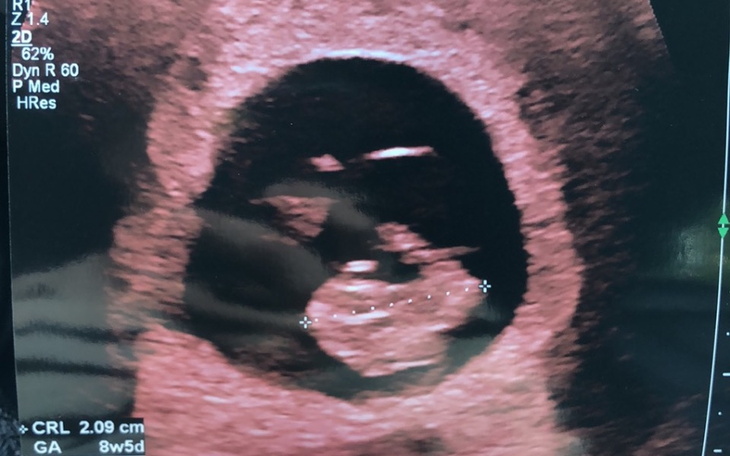

Witam mam na imię Aneta chciałabym aby moje dziecko miało dobry start wiem ze to marny pomysł prosić się lub zebrać o pieniądze bo czemu nie mogę sama wziąć się do pracy w końcu chciałam dziecka a wiec niedawno dowiedziałam się ze będę mamą jednak iż jestem obiera ryzykiem poronienia nie mogę pracować i tu tez dlatego postanowiłam prosić o pomoc . Polska to ciężki kraj do wychowywania dzieci oraz ciężki kraj do wychowywania dzieci inflacja w górę wszystko w górę ;/ jednakże może znajdzie się jakaś dobra duszyczka która wesprze mamę oraz jej nie narodzona miejmy nadzieje zdrową pociechę .